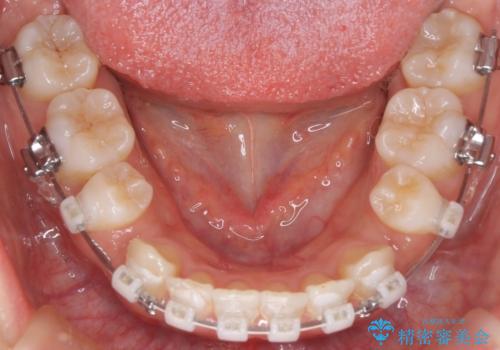

- 口元をさげたいという主訴で来院されました。4番の歯を4本抜歯し、審美装置にて治療をしました。

抜歯をしたことで口元の突出感が改善しました。約2年を予定していた矯正ですが、約1年という短い期間で終了できました。